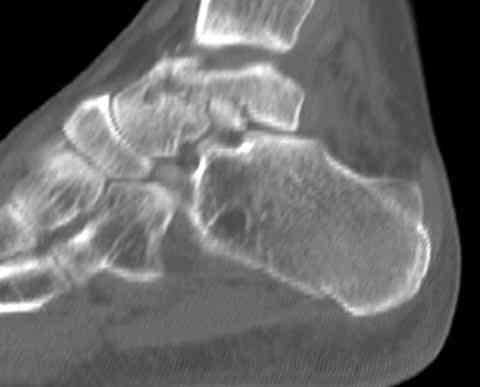

а основании двух видов ренгенограмм невозможно радикально решить о необходимости открытой репозиции или первичного артродеза.

Для оценки состояния нужны дополнительные исследования, например Canale или Broden ренгенограммы и Компьютерная томография.

При переломах тарана всегда имеется риск AVN, а классификация Hawkins поможет разобраться с предполагаемыми осложнениями.

На ренгенограмме не уловил многоскольчатость тарана, чтобы доказать, конечно, можно было исследовать на КТ, потом КТ дает ориентацию фрагментов.

Два фрагмента суставной поверхности тарана можно восстановить боковой компрессией шурупами и дополнительно костная пластика.

(кстати, на нашем случае была применена костная пластика-allograft crouton для заполнения дефектов)